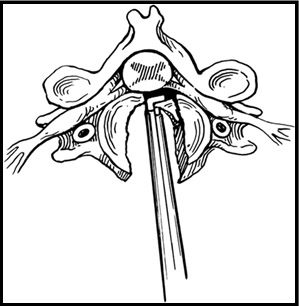

С этого этапа мною используется хирургический микроскоп, позволяющий различать все нервные структуры под увеличением до 16 раз. Это позволяется работать с тканями очень аккуратно, не допуская излишнего травматизма. Вначале удаляется мп диск, а затем и сама грыжа. (Рис.3) Операция заканчивается установкой межтелового импланта - кейджа (протеза диска). Кейдж (в переводе с английского «cage» означает «сетка») представляет собой титановый или пластиковый имплант, заполняемый собственной костной крошкой пациента или другим остеоиндуктивным (костеобразующим) материалом. Кейджи устанавливаются в полость диска, в результате чего восстанавливается высота последнего и соответственно высота фораминального отверстия (через который выходит спинномозговой корешок из позвоночного канала) для исключения сдавления корешка в указанном месте.

| Рис.3. Этап удаления грыжи мп диска вместе с диском. |